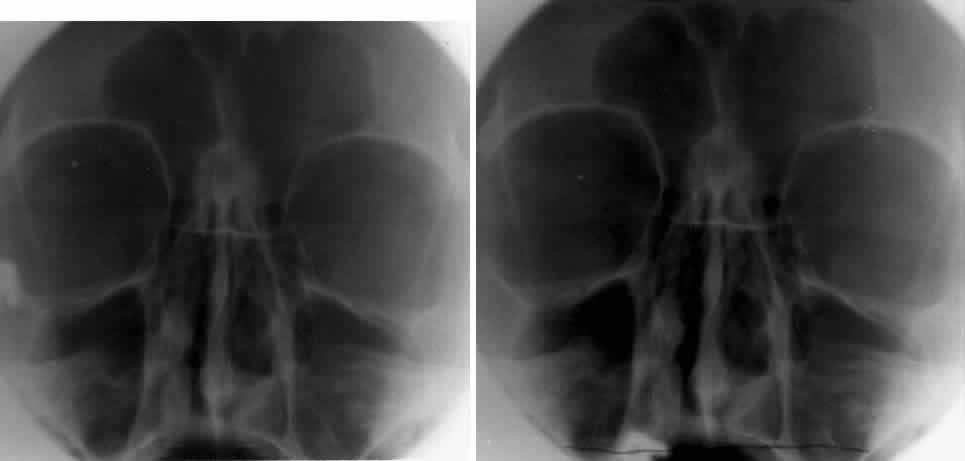

Because the orbit is in such close proximity to the larger bones of the skull, multiple shadows overlap one another and obscure some radiographic details. Numerous radiologic projections have been developed to evaluate the bony structures of the orbit and face.5,6 These various projections attempt to eliminate some of the obvious overlapping shadows and allow for better detail of the bony orbit. For maximal image clarity, the distance from the object to the x-ray cassette should be minimized and the distance between the subject and the x-ray beam maximized. This principle is demonstrated in Figure 1.

Fig. 1. In any projection the image detail is maximized using the minimal distance from the subject and the x-ray cassette. A. Anterior to posterior projection demonstrating decreased clarity and definition of anterior structures. B. Posterior to anterior projection showing the improved clarity of the anterior structures, such as the orbital rim and frontal sinus.